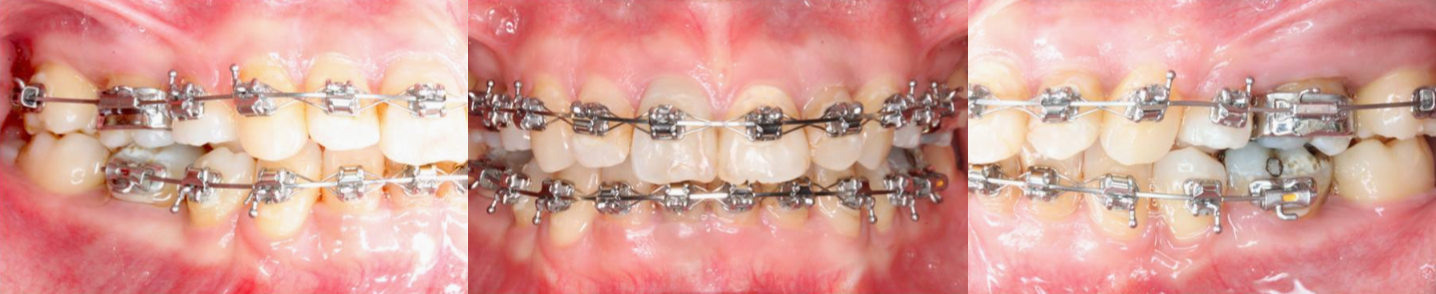

治療中

治療過程